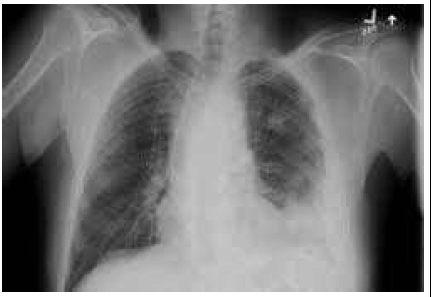

Uma paciente CLA, feminina, de 67 anos de idade, apresenta quadro de pneumonia bacteriana adquirida na comunidade. Durante internação para tratamento com antibioticoterapia endovenosa, evoluiu com manutenção de quadro inicial de dor pleurítica e com febre no 3.º dia de internação; seus exames laboratoriais estão sem alterações. Foram feitos exames complementares, conforme se vê na imagem a seguir. Foi realizada toracocentese, a qual evidenciou líquido purulento, pH < 7,20; DHL > 1.000 UI/L; e glicose < 40 mg/dL com bactérias presentes e cultura positiva.